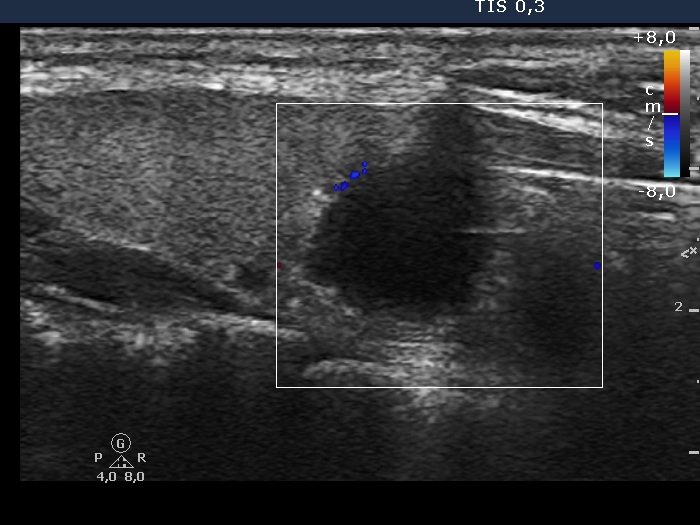

Parathyroid lesions - case 1269 (ultrasonographic picture 6)

Right lobe, longitudinal view, color Doppler mode.